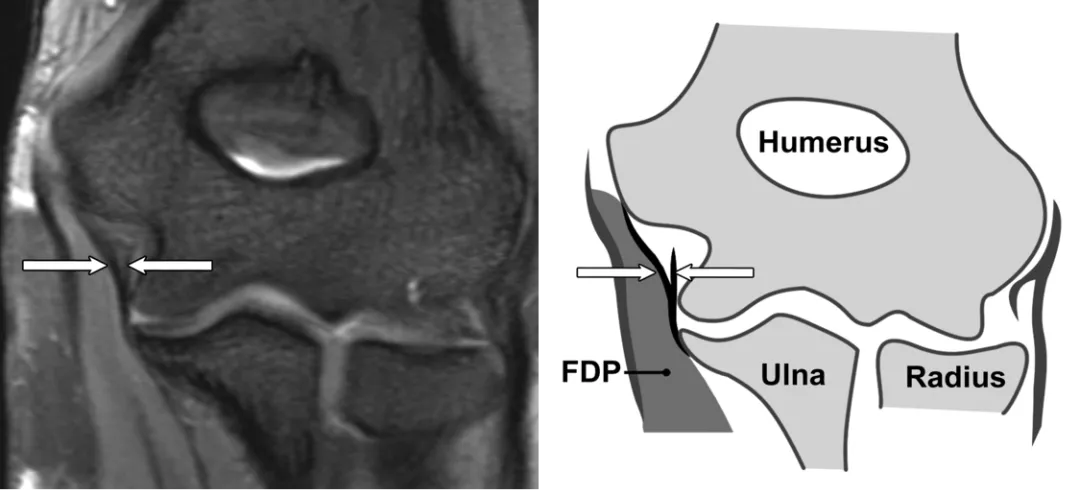

内侧副韧带前束

(a)在一名27岁女性中,内侧副韧带前束(箭头)具有条纹信号强度图案。(b) 对应的内侧副韧带前束示意图(白色箭头)。FDP = 指屈肌。(c)一名24岁男性冠状STIR磁共振成像显示内侧副韧带前束肱骨附着处信号增强(箭头)。